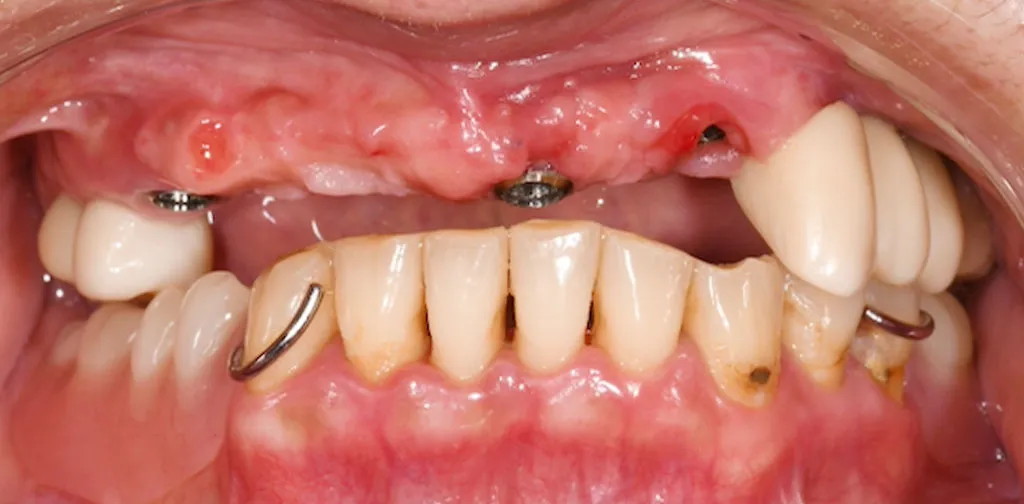

Before

After

複数本のインプラント治療

50代女性

治療期間:4ヶ月

費用:総額120.4万円(検査・診断・手術関連処置費用等を含む)

リスク:出血、腫脹、疼痛、神経麻痺、補綴物の脱落、破折、インプラント体の破折、咬合違和感、インプラント周囲炎など